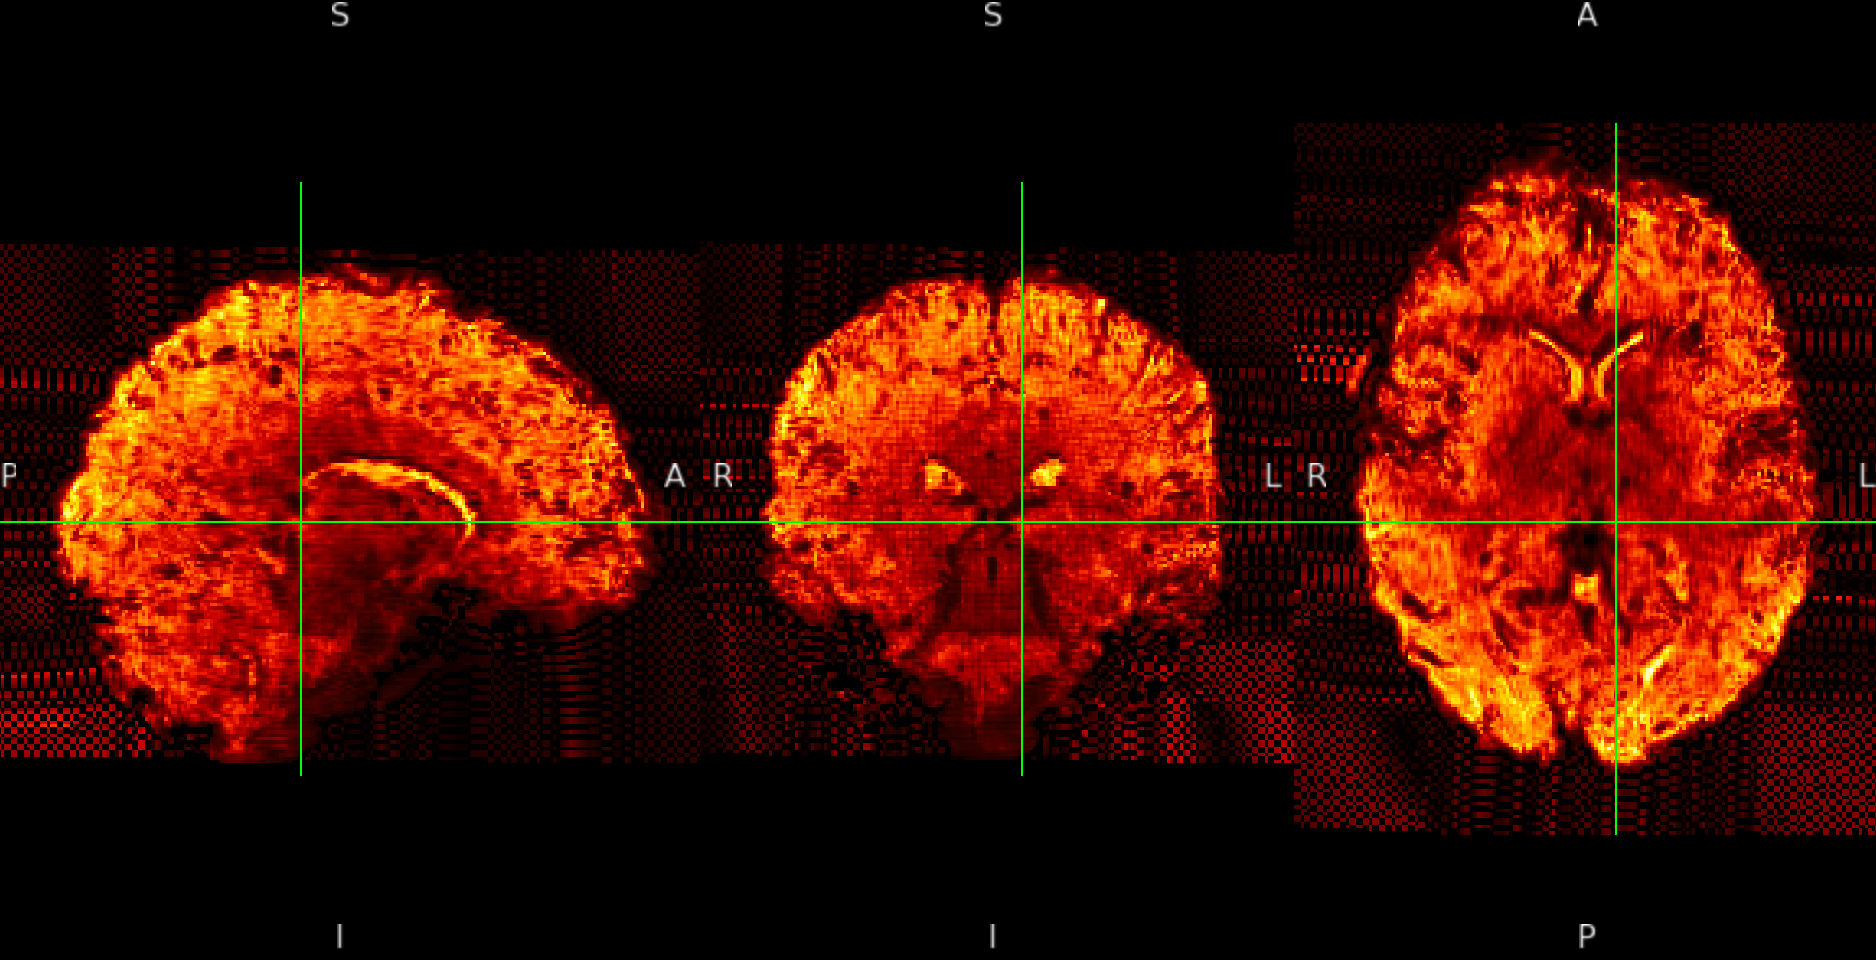

The pattern is not present in the raw data. It is not present either in the fmriprep native space. For example,

SE sequence in native:

ME sequence in native: